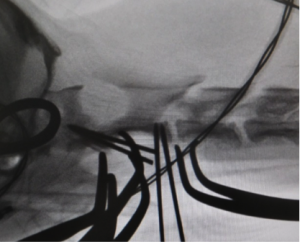

術中透視像

術中にCアームを使用してピンが脊柱管内に入り込んでいないかを確認しているところです。